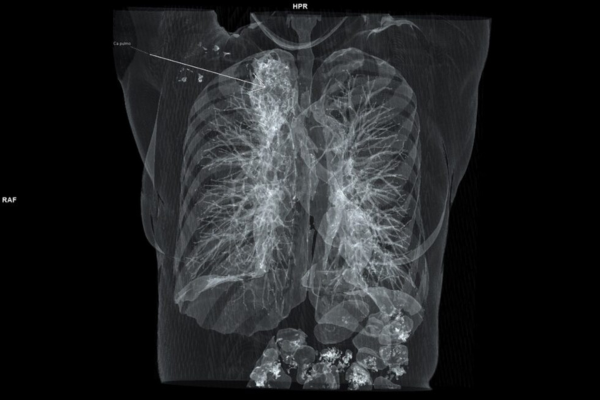

Skrining karcinoma pluća

Karcinom pluća je najsmrtonosniji karcinom na svetu i kod nas. U našoj zemlji godišnje umre gotovo 7000 osoba od karcinoma pluća, što čini 25% smrtnosti svih karcinoma.